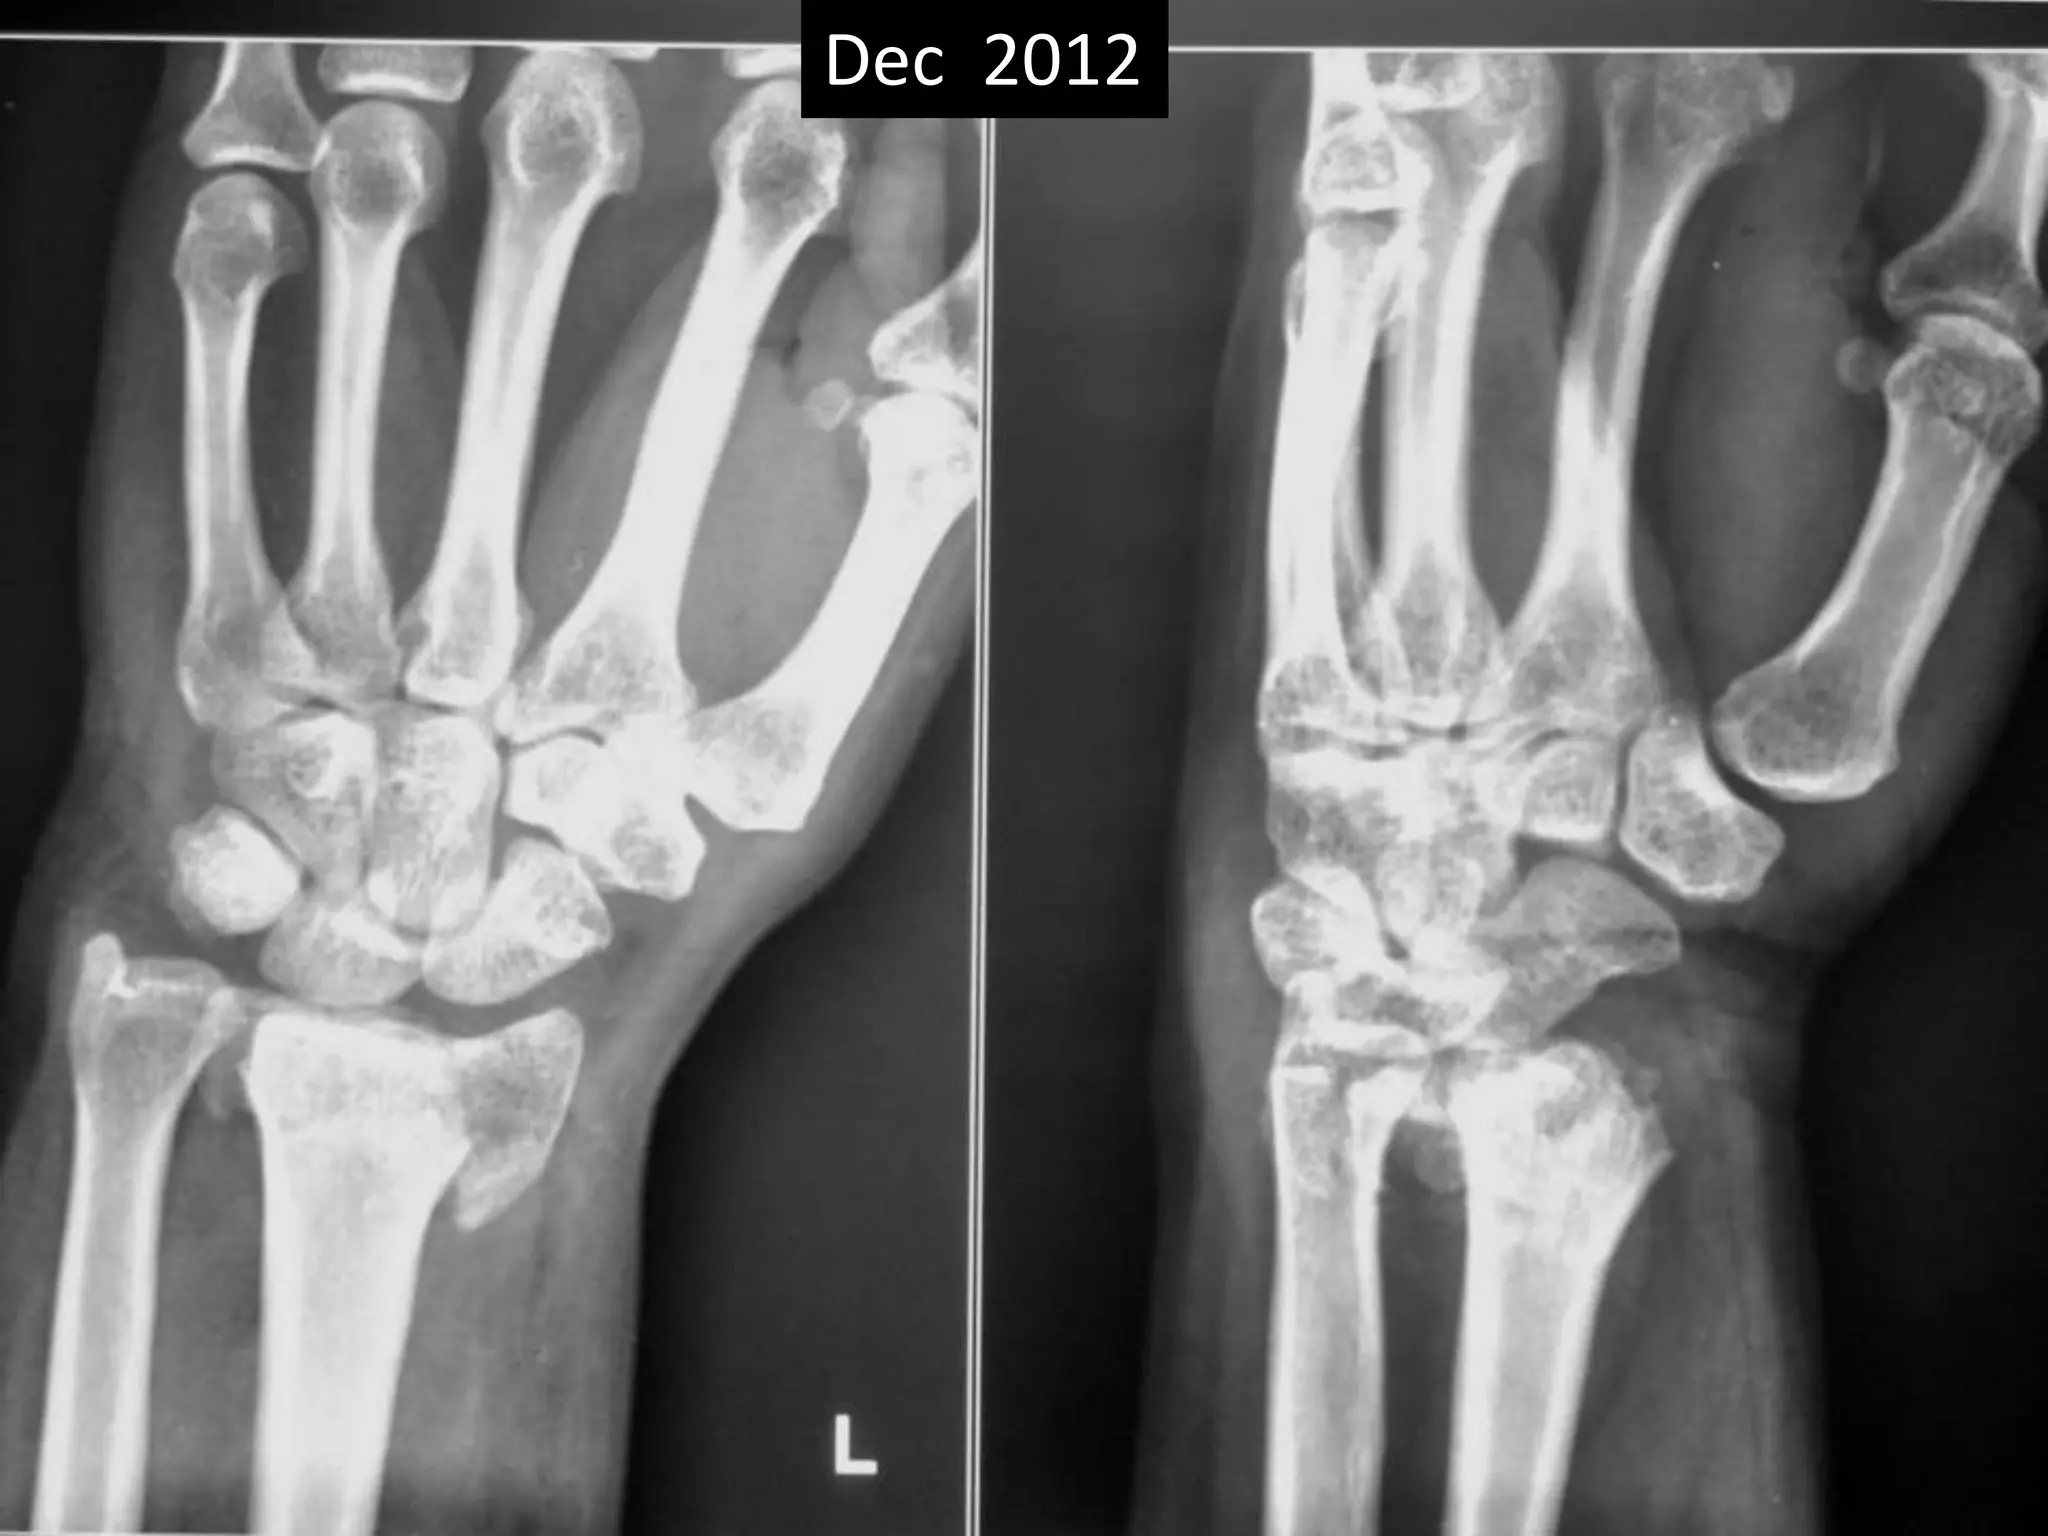

Case one

• 42 years old female.

• Low energy trauma.

• Fracture lower end radius

• Treated conservatively by closed reduction

and pop casting in Dec 2012.

Dec 2012

Case one •42 years old female. • Low energy trauma. • Fracture lower end radius • Treated conservatively by closed reduction and pop casting in Dec 2012.